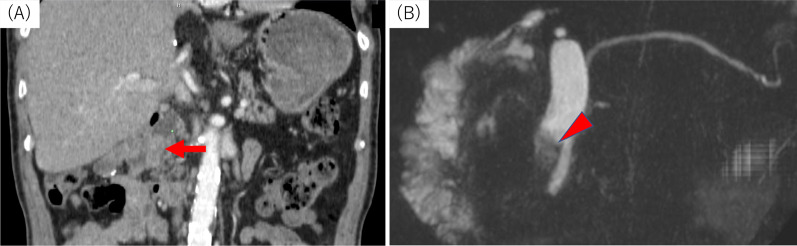

After surgery, annual assessments involving blood tests and abdominal CT scans were planned. At 12 postoperative months, the patient visited our outpatient department with fever. Laboratory tests revealed elevated total bilirubin levels (1.6 mg/dL), but normal carcinoembryonic antigen (2.2 ng/mL) and CA19-9 (25.5 U/mL) levels. CT/MRCP showed a 1.5-cm mass in the lower remnant common bile duct (Fig. 5A and B). We suspected IPNB recurrence and planned surgical intervention. The patient underwent subtotal stomach-preserving pancreaticoduodenectomy. Intraoperative examination of the main pancreatic duct was negative for malignant cells. By gross appearance, the papillary tumor with rich mucus was apparent in the lower part of the common bile duct. Microscopically, the lesion resembled the lesion resected in the previous surgery. The tumor consisted of non-invasive and invasive portions, the former being similar to the primary lesion. Immunohistochemically, MUC1 and MUC2 were negative and MUC5AC and MUC6 were positive, indicating a gastric-type IPNB, as before. The latter part of the recurrent lesion showed conversion from the non-invasive to the invasive type, and was considered to have acquired MUC1-positive and MUC5AC-negative characteristics in the process (Fig. 6). Multiple metastases were detected in the posterior pancreatic lymph nodes. No nerve infiltration was observed, and the surgical margin in the permanent specimen was negative. A postoperative pancreatic fistula (International Study Group of Pancreatic Fistula grade B) was identified, but improved with antibiotic therapy. The patient was discharged at 28 days after surgery.

Fig. 5.

Contrast-enhanced computed tomography and magnetic resonance cholangiopancreatography findings for the recurrent lesion. A Contrast-enhanced computed tomography findings revealed a 1.5-cm mass in the lower remnant common bile duct at 16 months after the first surgery (arrow). B Magnetic resonance cholangiopancreatography findings identified the tumor as a defect in the lower remnant common bile duct (arrowhead)